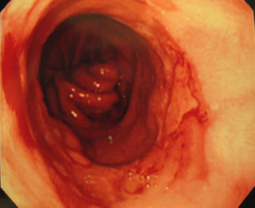

胃カメラ検査でも胃と食道のつなぎ目に近い食道粘膜は、ほぼ全周にわたって赤くただれ、粘膜が剥がれ落ち、潰瘍を作っていました(右図)。この潰瘍からは悪性の細胞は見つからなかったので、胃酸が逆流してできた潰瘍と考えられます。